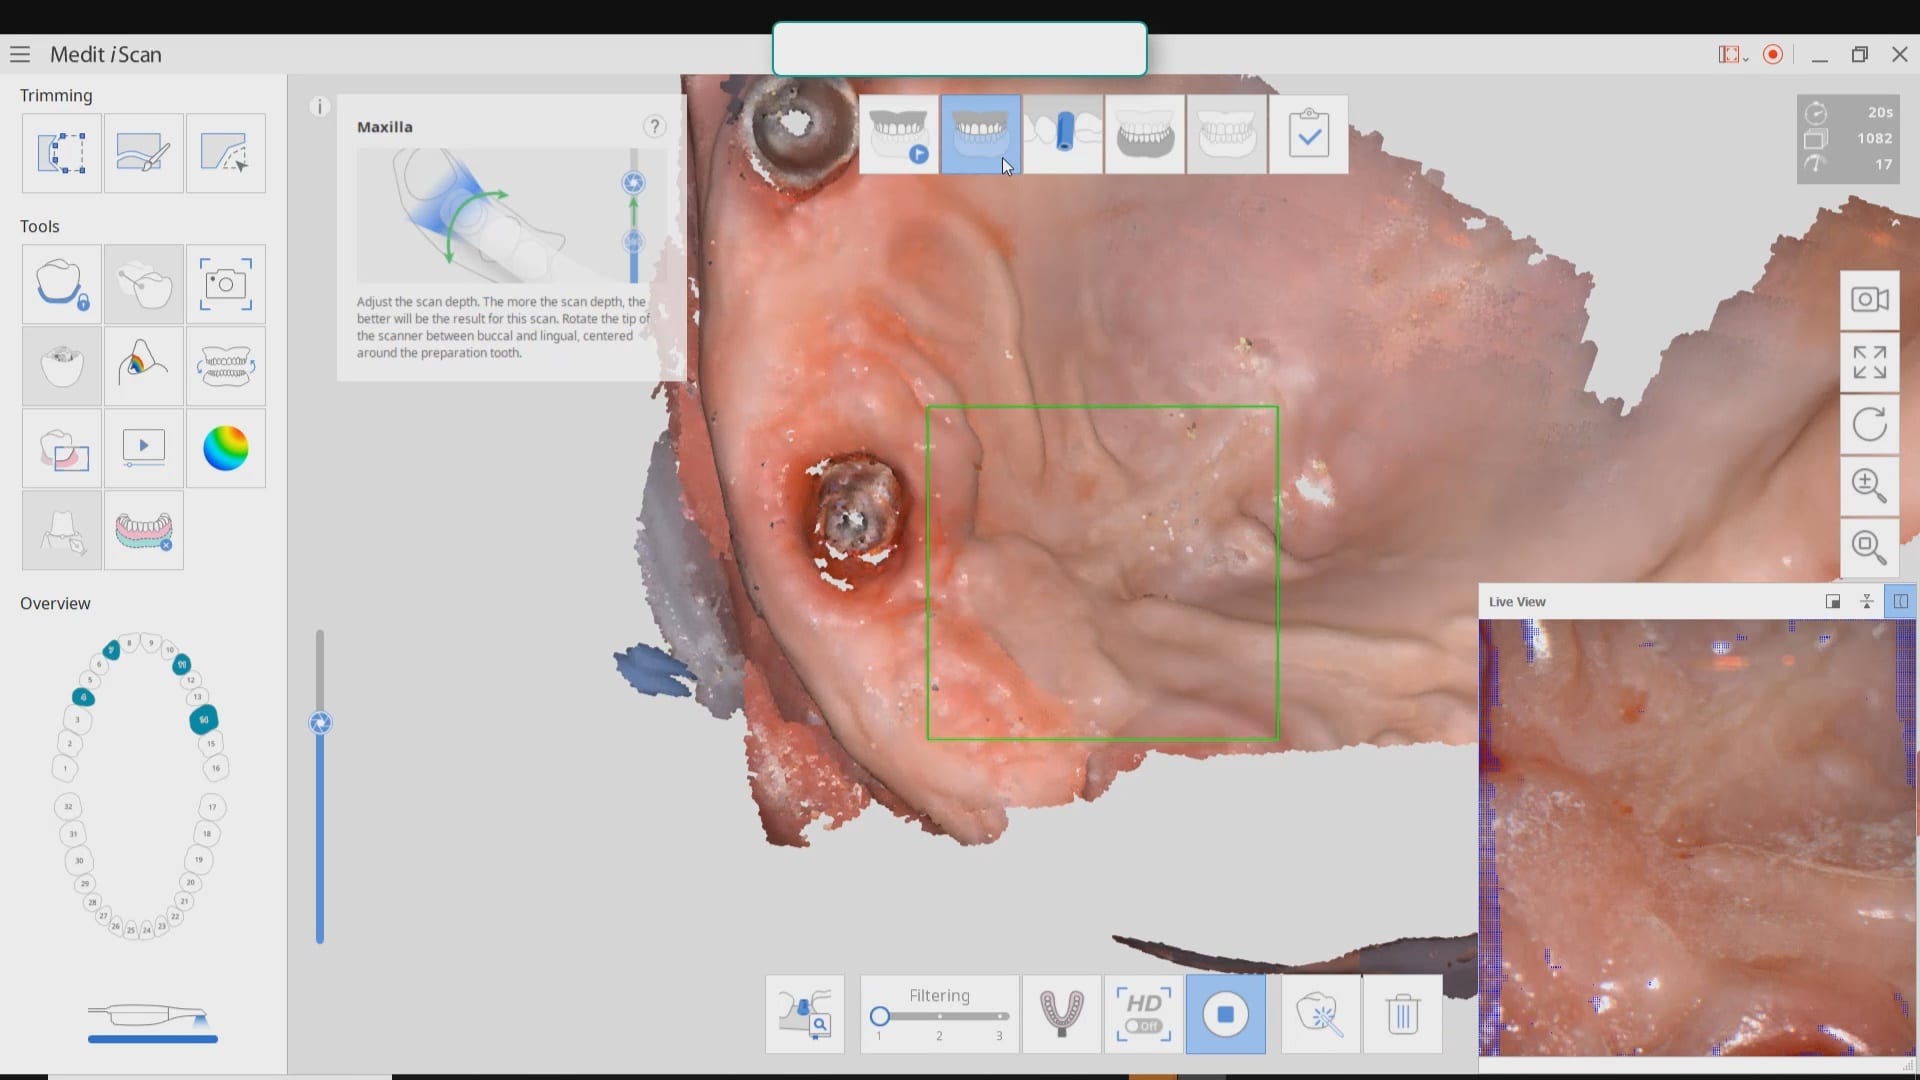

Live Intra-Oral Scan Verification Jigs for Full Arch Scans and Global Accuracy

October 25, 2019This is a detailed video demonstration that shows you how to capture full arch scans for multi unit implant cases in edentulous jaws and, more importantly, how to assess its […]